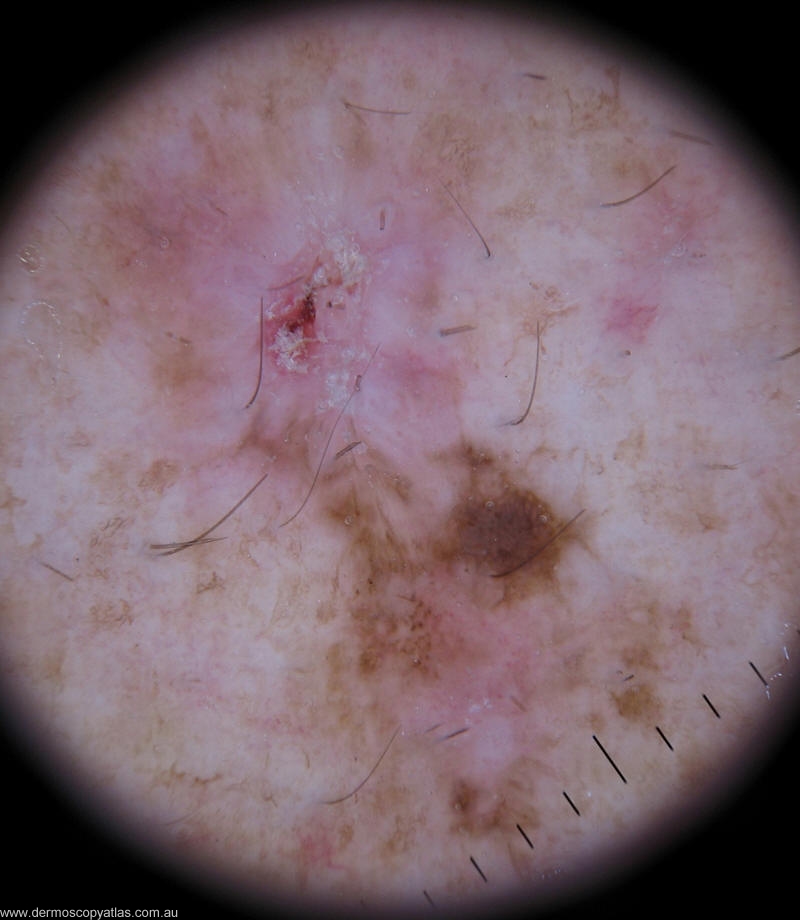

Case 2 52 y.o man presented for his annual melanoma follow up.He has history of Clark Level III melanoma excised from his left flank 15 years ago.Since then he has few BCCs excised from his face and trunk.

Question: What is your diagnosis of this lesion?

Answer: Melanoma in situ with regression